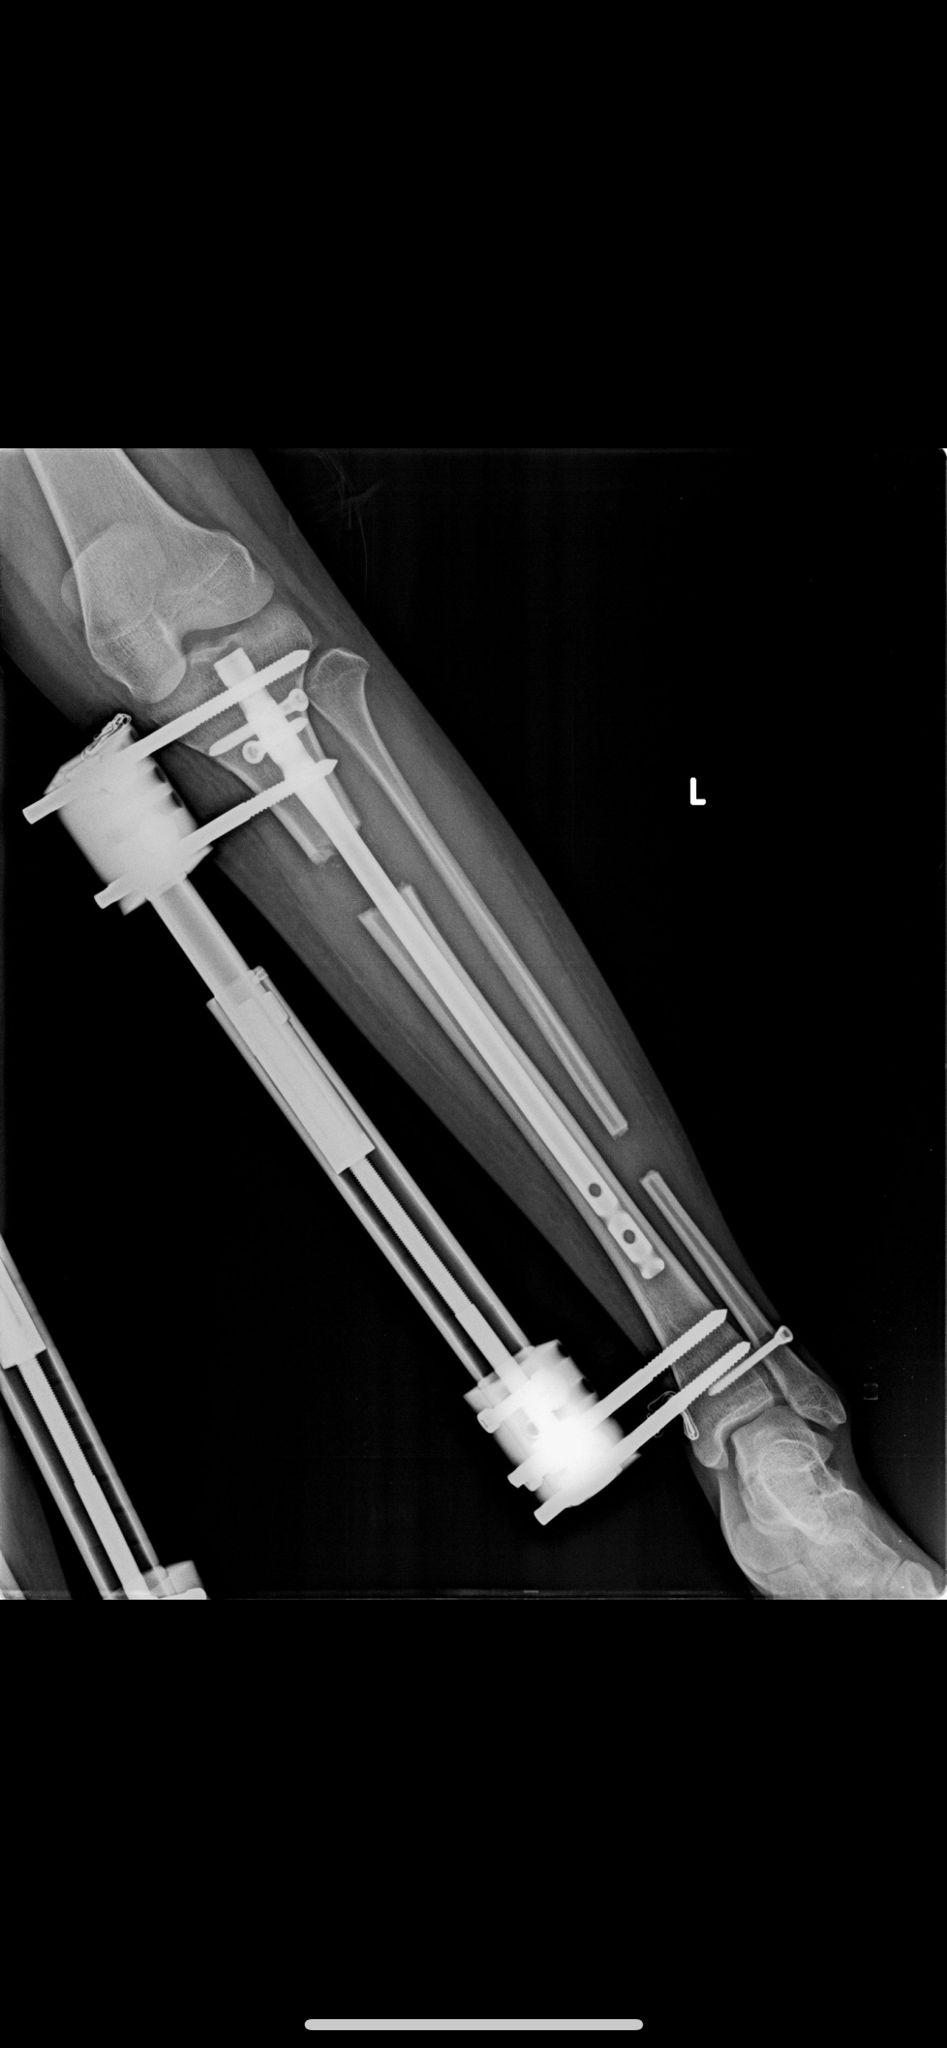

Lon Yöntemi

LON Yöntemi (Lengthening Over Nail) ile Femur ve Tibia Uzatma – Tıbbi Açıklama